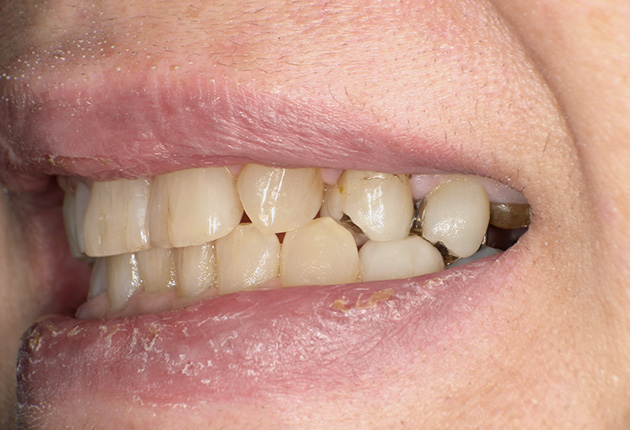

90分の治療で銀歯の状態からキレイな状態になります。噛み合わせの調整や審美面も使用しながら合わせます。

良く噛めて安心と、ご満足いただき大変嬉しく思います。笑顔も一層素敵になりました。

| 治療内容 | 欠損部インプラント 不正咬合に対し不良補綴のやり直しと合わせて咬合再構築 |